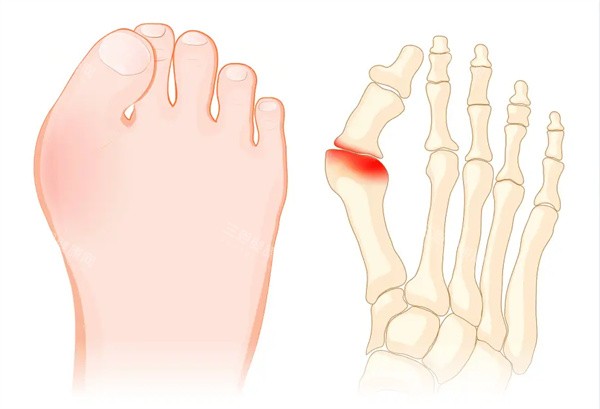

身边好多人受拇指外翻困扰 —— 穿鞋磨脚、走路疼,有的甚至影响运动和日常。

基本情况:穿高跟鞋 5 年,右脚拇指慢慢外翻,穿单鞋磨得发红,久走还疼,怕越拖越重

基本情况:遗传妈妈的拇指外翻,右边比左边重,穿平底鞋都磨脚,怕影响以后穿婚鞋